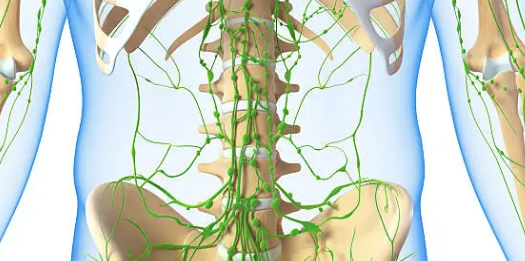

9. 림프절 종대

목, 겨드랑이, 사타구니 등에서 림프절이 붓고 커지는 증상이 나타날 수 있습니다. 이는 림프계에 백혈병이 영향을 미쳐 림프절 비대가 발생하는 것입니다.